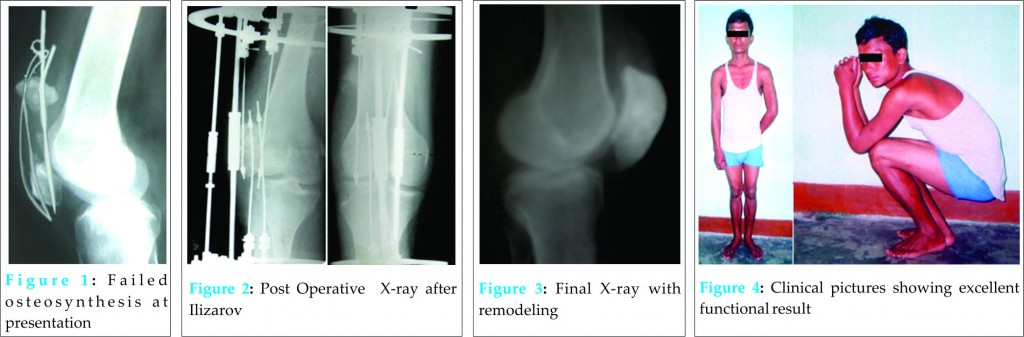

A 27 years old male sustained transverse fracture of the patella with gross displacement while playing football. The fracture was subsequently stabilized with tension band wiring with two Kirschner wires (K-wire ) & figure of eight stainless steel wire. The immediate post operative period was uneventful. He was discharged after stitch removal with knee support and was advised partial weight bearing with knee bending exercises in between. However, he indulged in heavy manual work including bicycling after 15 days of surgery. This led to loosening of implants and failure of reduction. He reported after 2 months of failure with pain,swelling and stiffness of the knee joint. X-rays revealed wide displacement of the fragments with loose implants (Fig 1).

The options for such a case were either patellectomy or apposing the fragments by some means. Patellectomy would lead to difficulty in apposing the ligaments as there were gross displacements of the fragments leading to contracture of soft tissues on either side of the patella. Apposing the fragments would require extensive soft tissue dissection and lengthening of the quadriceps tendon resulting in extensive scarring and stiffness. As we were accumulating experience by using Ilizarov in various situations, we opted for it to mend the difficult situation in this case. We felt gradual docking with slow stretching of the soft tissue without any dissection would be the perfect choice for the case. After removing the implants, the fracture margins were cleared of fibrous tissue taking care not to remove any bone. As acute docking was not possible, sub-acute docking was contemplated on the table. Opposing olive wires, 2 in number on either fragments (total 4 in number), attached to traction units were passed through the fragments which were mounted on two full rings on either side (joining two half rings). The rings were fixed to distal femur and proximal tibia by wires and interconnected with threaded rods.The fragments were brought together as close as possible on the table by turning the nuts on the traction units (sub-acute docking); subsequently gradual docking was done with the help of traction units till X-ray showed complete contact. The traction unit consisted of slotted threaded rod with mounted K-wire which was held in place by nuts [3]. These units were mounted on the ring by male post. After docking, as confirmed by X-Ray, compression was applied across the fracture site at the rate of 1/4th turn every 3rd day till one millimeter of compression was achieved (Fig 2). Full weight bearing was allowed as pain permitted. Patient was followed up every 2 weeks looking for pin site infections and loosening of the compression achieved. Assembly was removed when X-ray showed complete healing.

There were no major pin site problems. The patient was comfortable with the system.He was happy that he could take full weight on the injured limb. Only drawback was that knee flexion was not possible till the apparatus was on. Fracture united in 2 months time. Initially after removal of the apparatus,there was restriction of movements at the knee joint. He was managed with physiotherapy in the post removal period. The range of movement showed improving trend so that at one year follow up, he could squat completely. X-ray at the last follow up (at 4 years) showed remodeling of the articular surfaces (Fig 3). There was no pain and the patient could perform all manual works as required in his profession including cycling, carrying weights, and running. He indulged in playing football as before without any problem (Fig 4).